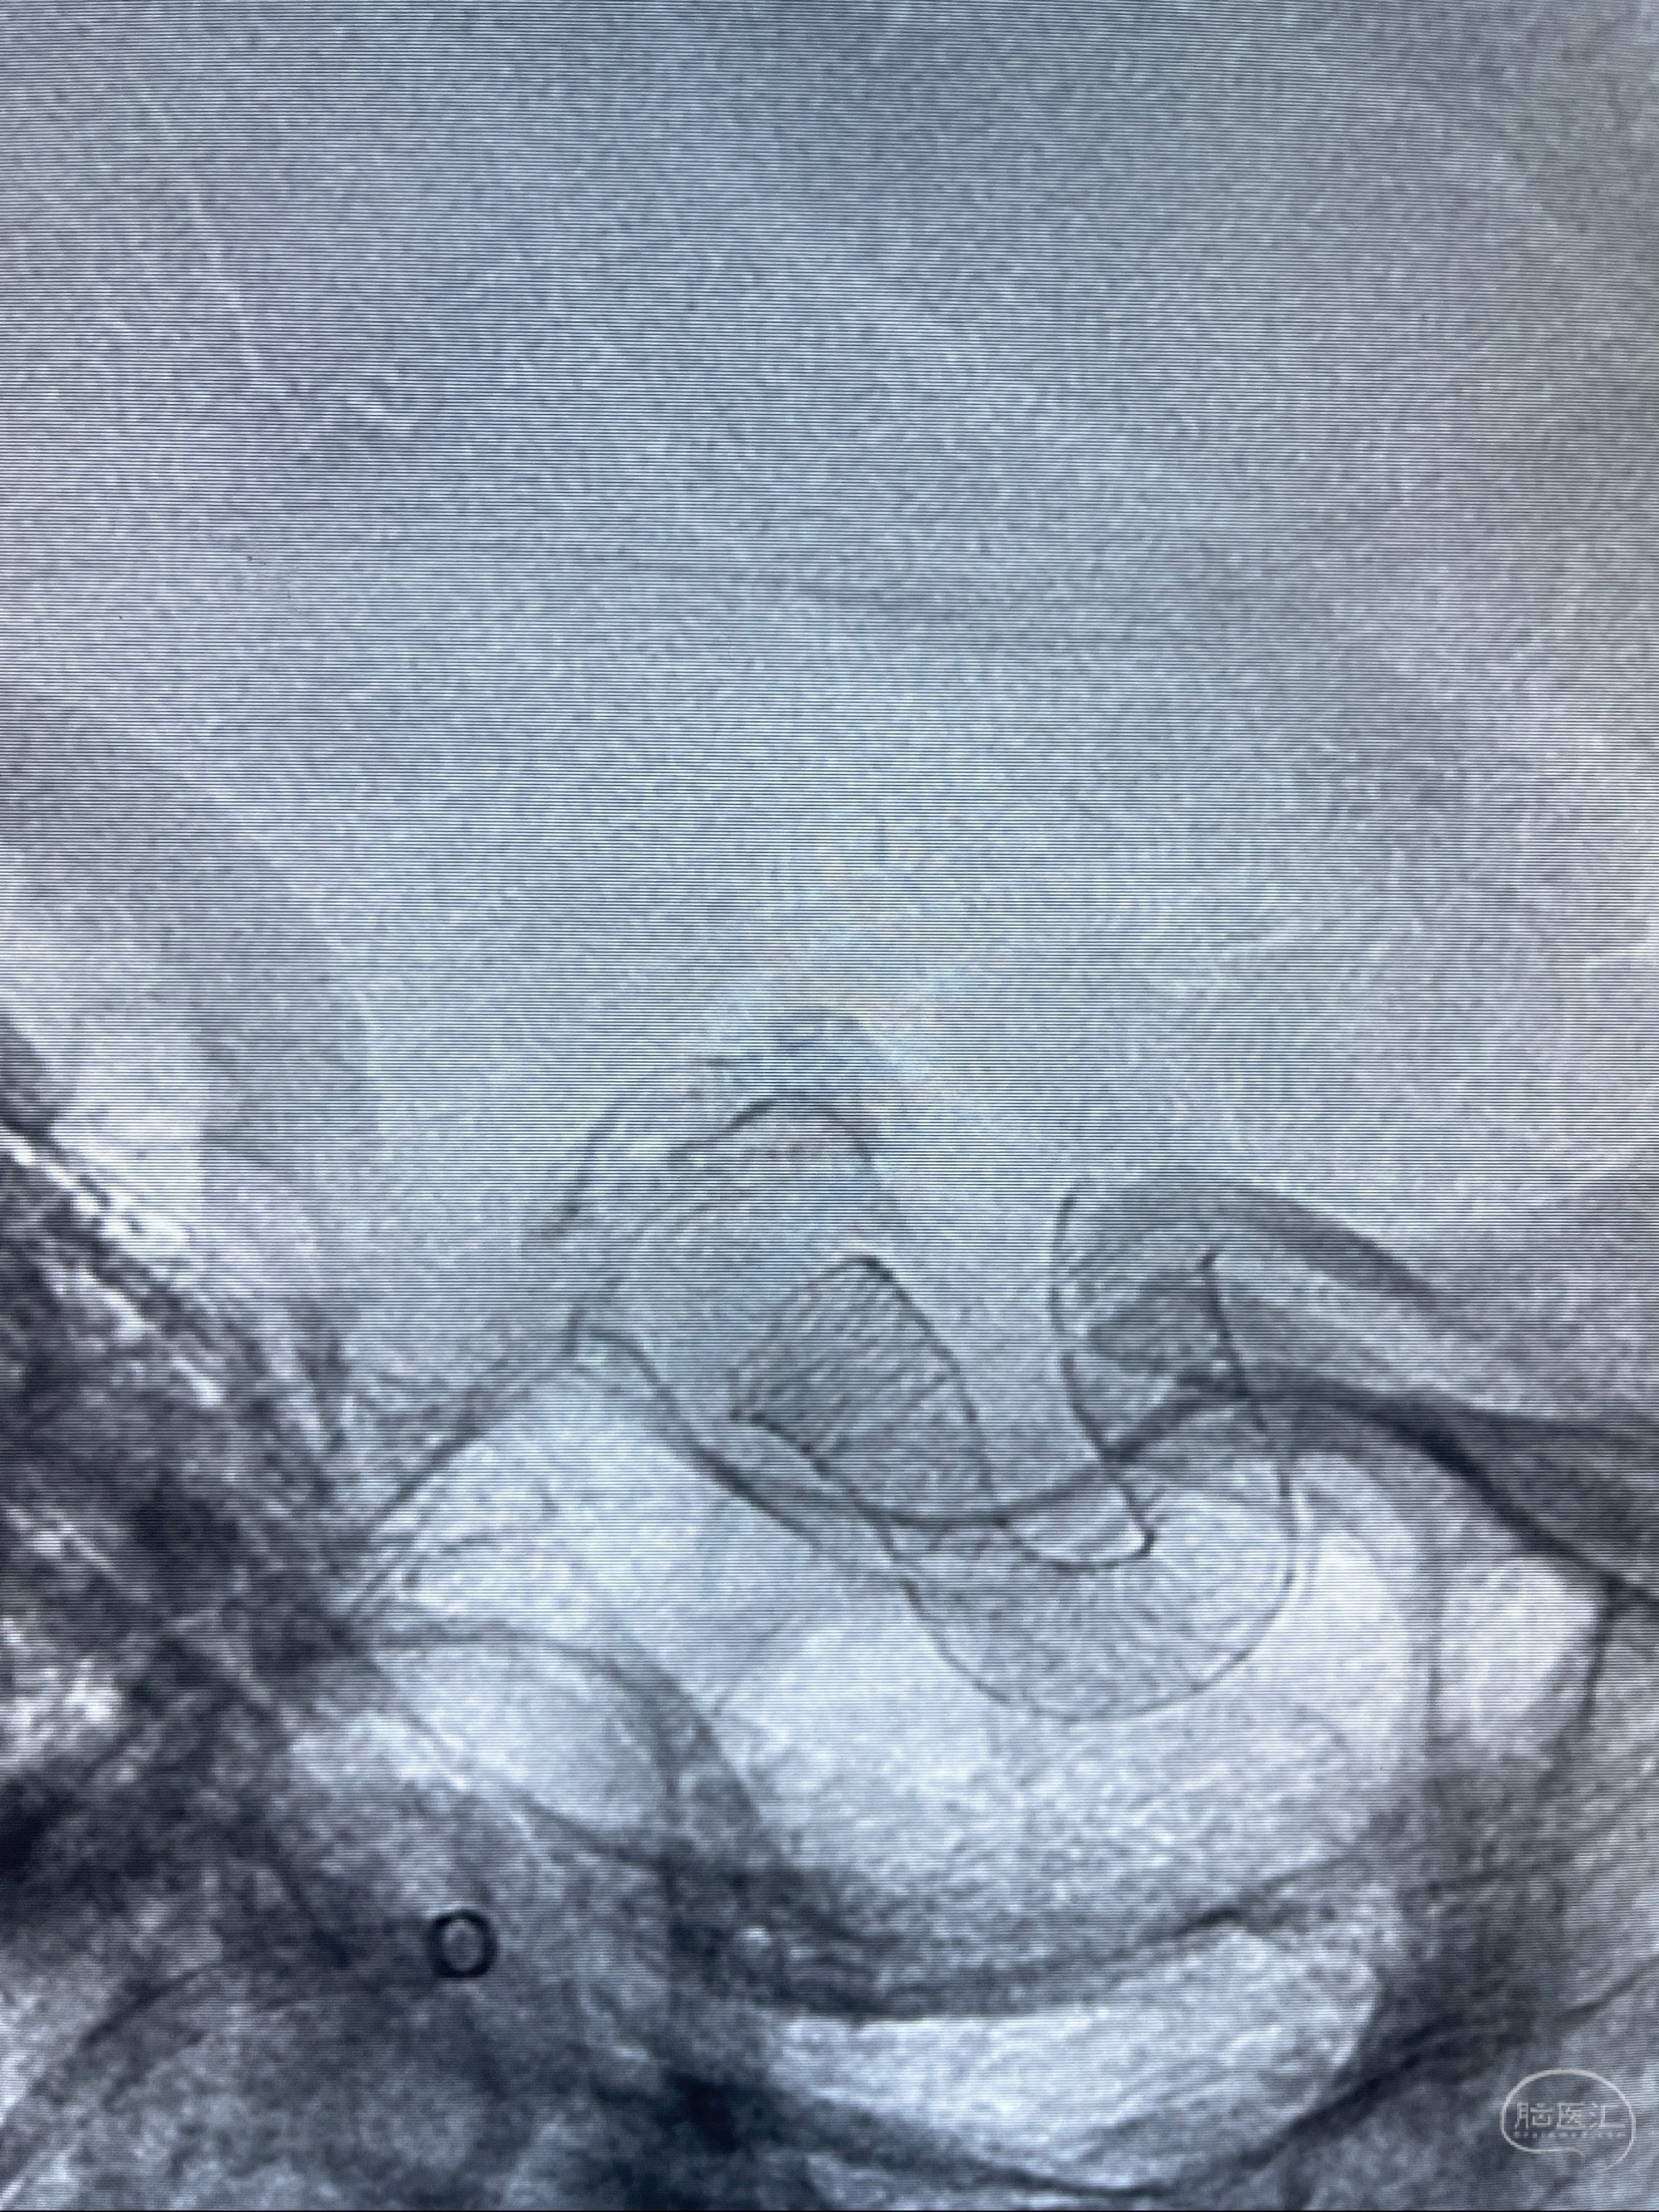

2023-08-01全麻下行双侧颈眼动脉瘤支架辅助栓塞

- pipeling4.5-20mm

- pipeline 4.0-20mm

手术顺利,麻醉苏醒佳,遵嘱动作